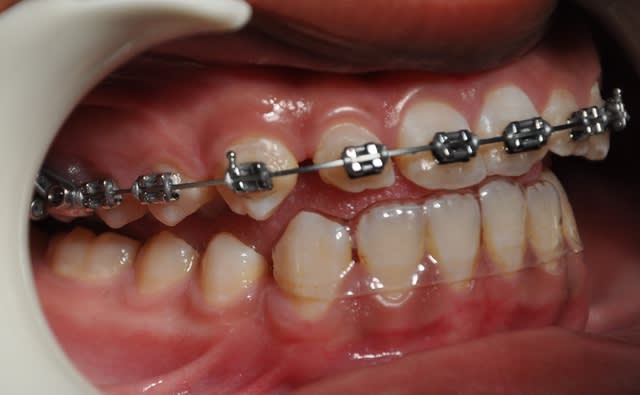

2ème étape

Dsc 0004 lwlouj - Eugenol

Dsc 0003 kobtob - Eugenol

Dsc 0005 pfdneo - Eugenol

Dsc 0006 pndvvp - Eugenol

Dsc 0001 hztqqg - Eugenol

Dsc 0002 b3d098 - Eugenol